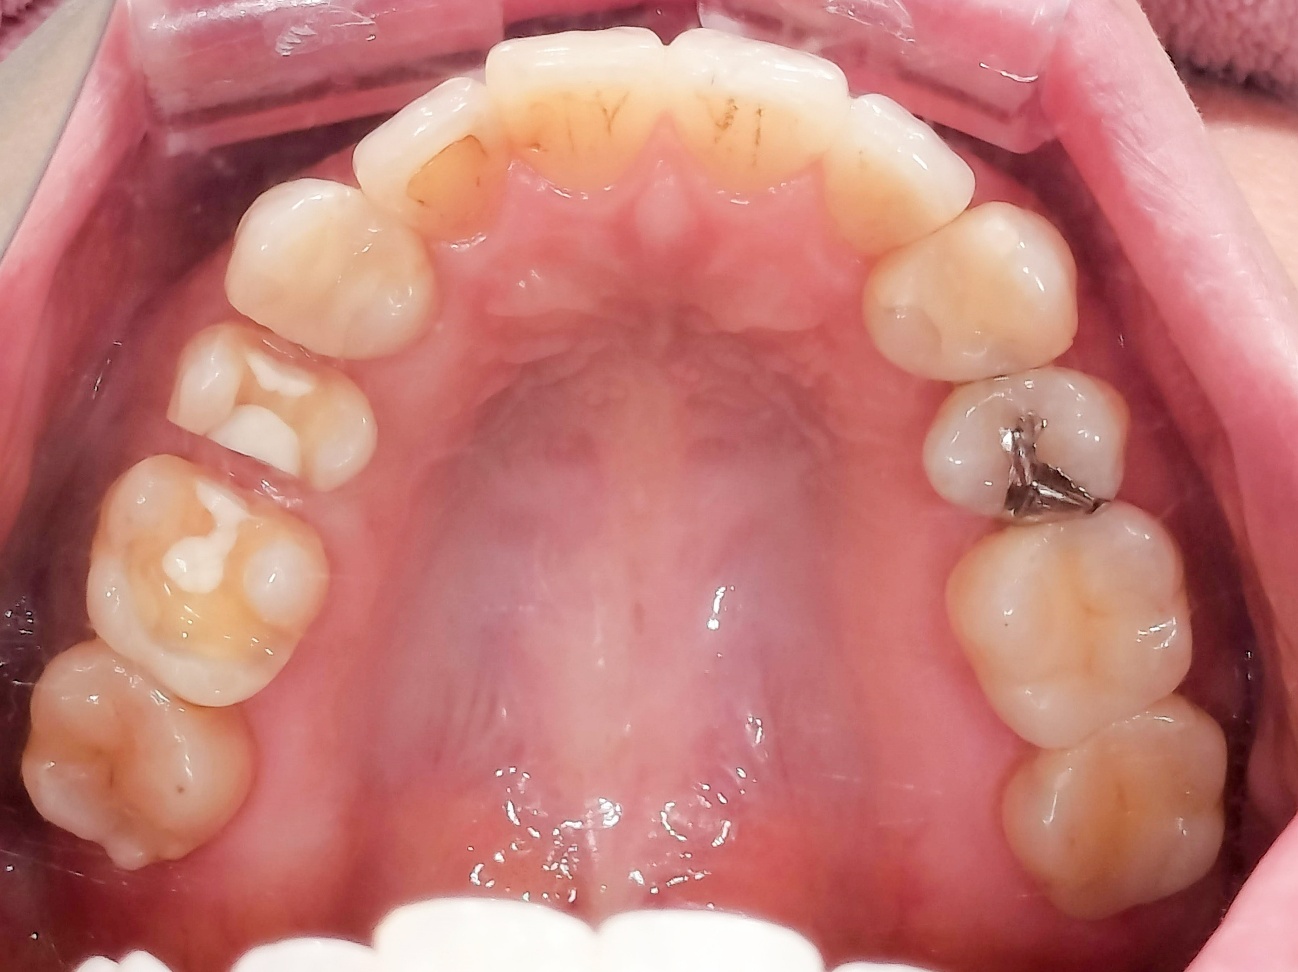

奥歯の噛み合わせと前歯の歯並びを同時に改善した症例(インビザライン+ジルコニア)

【治療前の状態】

患者様は、奥歯でしっかり噛めないことと、前歯の歯並びの乱れを気にされ来院されました。診査の結果、前歯部の叢生(歯並びの乱れ)と、臼歯部の離開咬合(奥歯がしっかり噛み合っていない状態)が認められました。また、臼歯部には古い金属修復物が装着されており、機能面だけでなく審美面においても改善が必要な状態でした。

【治療後】

前歯の歯並びが整い、見た目の改善が認められました。また、奥歯でしっかり噛める状態となり、咬合機能の回復が得られています。

【治療のポイント】

本症例では、歯並びの改善だけでなく、噛み合わせの回復と審美性の向上を同時に行っています。当院は一般歯科と矯正治療の両方に対応しているため、矯正治療後に別の医療機関で補綴治療を行う必要がなく、一貫した治療計画のもとで治療を完結することが可能です。また、奥歯の噛み合わせを矯正治療のみで改善する場合、治療期間が長くなることがありますが、本症例では補綴治療(アンレー)を併用することで、比較的短期間で咬合の改善を行いました。さらに、古い金属修復物をジルコニアに置き換えることで、見た目の改善と機能性の両立を図っています。